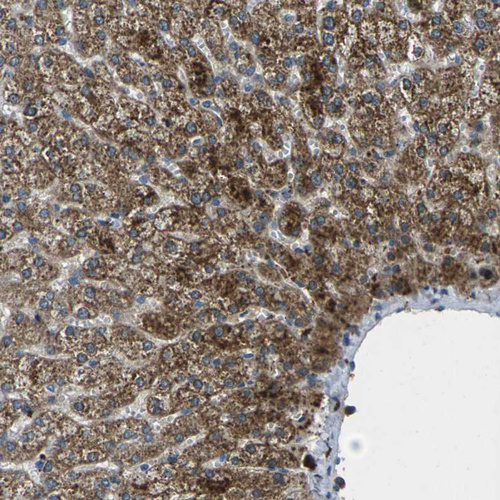

Immunohistochemical staining of human liver shows moderate granular cytoplasmic and membranous positivity in hepatocytes.